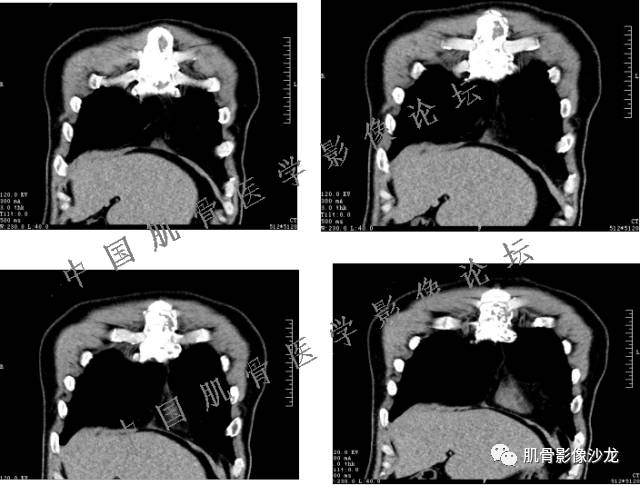

患者2月前无明显诱因下感右腿疼痛、麻木,疼痛呈持续性,发作时无法行走,休息后可缓解。当时无明显肿块,患者遂至当地医院就诊,查X片见右髂骨骨质破坏。6周前患者自觉右髋部渐大肿块,初肿块较小,后肿块逐渐增大,现肿块约12*10cm大小,有压痛。患者遂至我院就诊,查MRI:右髂骨异常信号,伴软组织肿块。ECT、肺CT未见转移。现患者为求进一步治疗,门诊拟“右髂骨肿块 ”收治入院。 患者发病来,神清,精神可,胃纳夜眠可,二便无殊,体重无明显变化。

信号 飞鹰行动:的确应该考虑软骨类肿瘤

飞鹰行动 : 软骨肉瘤内也有纤维组织的

飞鹰行动 : 第一列可以看见T2小结节样高信号,周围有纤维组织环绕

高回青 : 另外还可以见到扇贝状分叶

1、软骨肉瘤可以有膨胀性骨质破坏(病例3,4),可以有溶骨性骨质破坏(病例2),局部皮质因为破坏变薄,中断 ;

2、软骨基质T2WI高信号,软骨小叶分叶状,也就会出现高老师提到的骨内膜扇贝形压迹。一般认为骨内膜扇贝形压迹超过骨皮质厚度的2/3是软骨肉瘤在长管状骨的特征性表现。如上图。3、软组织肿块或肿胀;